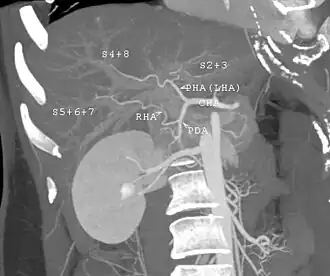

The vast majority of liver transplants use the entire liver from a non-living donor for the transplant, particularly for adult recipients. A major advance in pediatric liver transplantation was the development of reduced-size liver transplantation, in which a portion of an adult liver is used for an infant or small child. Further developments in this area included split liver transplantation, in which one liver is used for transplants for two recipients, and living donor liver transplantation, in which a portion of a healthy person's liver is removed and used as the allograft. Living donor liver transplantation for pediatric recipients involves removal of approximately 20% of the liver (Couinaud segments 2 and 3).

In a typical adult recipient LDLT, 55 to 70% of the liver (the right lobe) is removed from a healthy living donor. The donor's liver will regenerate, approaching 100% function within 4–6 weeks, and will almost reach full volumetric size with recapitulation of the normal structure soon thereafter. It may be possible to remove up to 70% of the liver from a healthy living donor without harm in most cases. The transplanted portion will reach full function and the appropriate size in the recipient as well, although it will take longer than for the donor.[17]